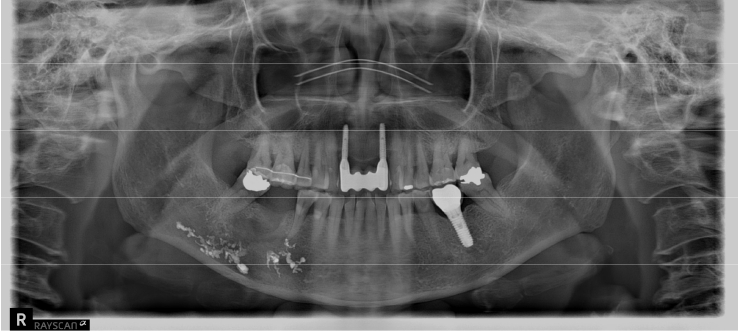

An 18-year-old male developed numbness in the right lower lip, gingiva, and chin following endodontic treatment of the mandibular right first molar (#46) at a military hospital 2 weeks ago. A panoramic radiograph and multi-detector computed tomography (MDCT) revealed extruded Calcipex II in proximity to the IAN (Fig. 6). Neurologic testing confirmed severe hypoesthesia in the right mentum region. Thermal discrimination was absent across a broad area of the right lower lip and chin. The patient’s subjective discomfort was rated as VAS 2. The patient underwent foreign body removal, nerve transposition, and bone grafting under general anesthesia (Fig. 7). At one-week postoperative follow-up, neurosensory testing showed little to no improvement. At the five-month follow-up, repeated neurosensory testing demonstrated meaningful improvement in directional discrimination and pin-pressure nociceptive discrimination, despite the continued presence of hypoesthesia. At the 17-month follow-up, testing revealed further improvement, including recovery of static light touch sensation, with overall symptoms classified as mild hypoesthesia. However, the patient reported worsening subjective discomfort, with a VAS 5, reflecting a discordance between objective sensory recovery and subjective symptom persistence.- Case 5